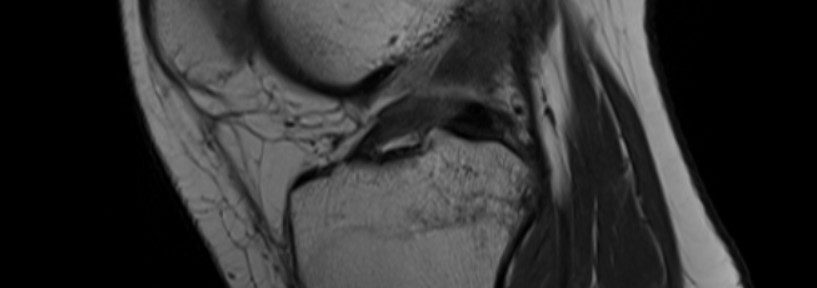

RM de control (~3 meses) y ACLOAS:

Tras 3 meses de Ejercicios Evo-Devo se realizó una RM de control. Los tres lectores calificaron el LCA nativo como ACLOAS 1.

[Notas ACLOAS (LCA nativo)] 0 = normal (baja señal, espesor y continuidad regulares) / 1 = engrosamiento y/o alta señal intraligamentaria, pero la forma y la continuidad son normales / 2 = adelgazado o elongado, pero con continuidad preservada / 3 = defecto o pérdida completa de continuidad.

Primera RM y clasificación de Ihara:

Tres especialistas en imagen independientes releyeron la primera RM: clasificación de Ihara “Tipo II para dos lectores, Tipo III para uno”.